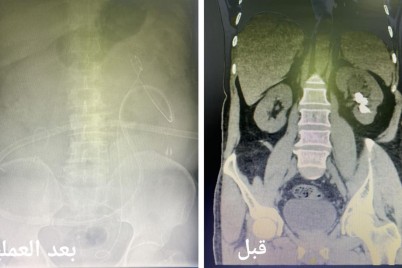

أوضحت المديرية العامة للصحة بمنطقة الجوف أن فريقاً طبيًّا نجح في إنقاذ حياة طفلة ابتلعت قطعتين معدنيتين. وأضافت “صحة الجوف”...